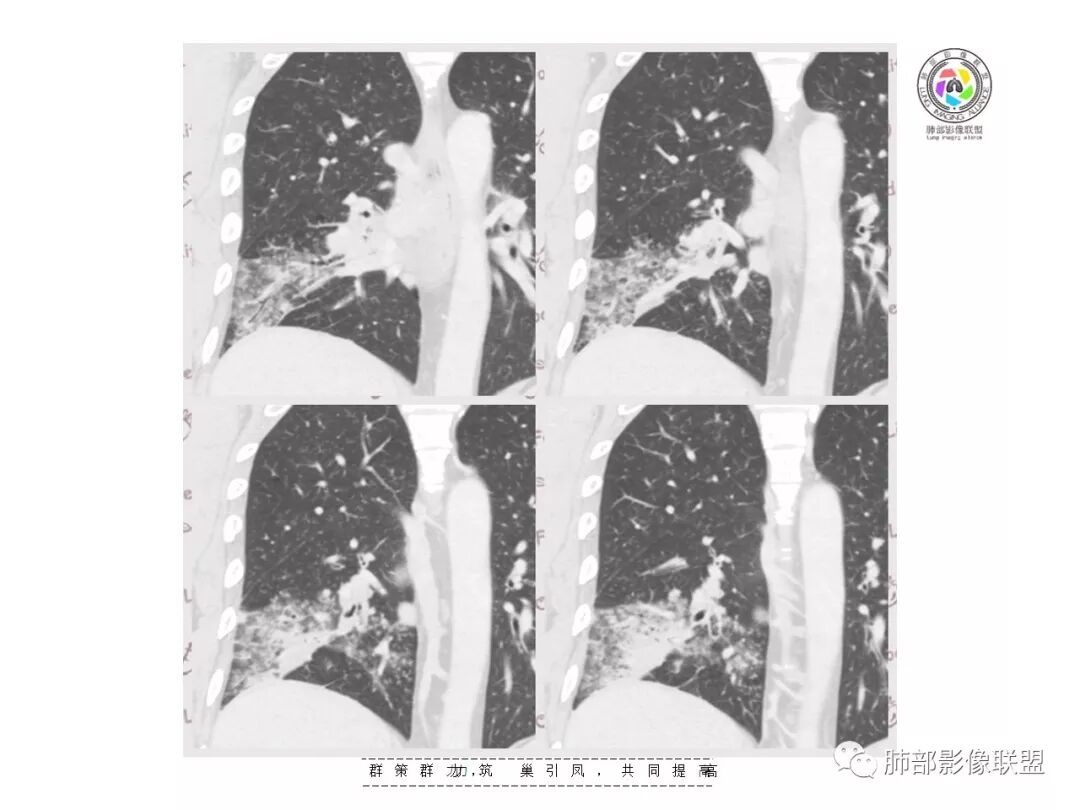

【影像资料】

张帅,首医附属潞河医院呼吸科:右肺下叶支气管开口明显狭窄,外基底段远端实变,内可见支气管征,周围可见弥漫结节样变,周围毛玻璃影,小叶间隔增厚,部分支气管壁不规则增厚,部分肺野可见小囊性变,壁部分增厚,右肺门明显增大,病灶与胸膜脂肪间隙增大,考虑恶性病变,腺癌。

王秀仙东宁市第二人民医院影像科:晨读:右肺下叶实变及磨玻璃影,边缘有收缩有膨隆,部分支气管进入扭曲扩张,磨玻璃影边缘清晰,实变影明显强化,内可见血管造影征,纵膈及肺门淋巴结肿大并强化,考虑粘液腺癌。

登封市三康医院(刘权威):右下肺肺不张,磨玻璃影,边缘清楚,空气支气管征,增强有强化,纵膈及右肺门淋巴结肿大并强化,考虑恶性肿瘤,粘液腺癌可能。

这是支气管扩张,老病灶,周围实变不明显,按理应该独立出来

下叶外基底段为主实变,周围GGO

分布:沿支气管段、亚段朝外蔓延分布

实变区边缘收缩,支气管走形自然

但是我们也可以看到实变区很多地方没看到支气管,也就是支气管在实变区分布不均匀,提示有些地方支气管腔内有物质填塞,显示不清

GGO边界大部分不清楚,内有树芽征,中央间质均匀增厚

这个是前基底段的,支气管扩张区域的,前面提了,独立出来

支气管没看到明显的堵塞

但是应该是与受压局部狭窄,导致远端引流不畅有关